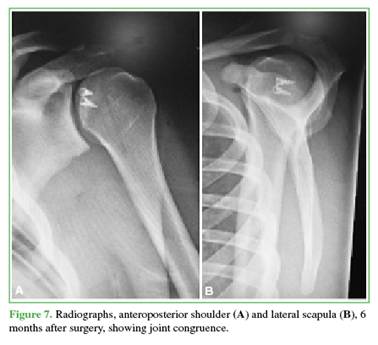

Operative time ranged from 80 to 150 minutes (mean, 100). There were no redislocations, infections, or signs of instability in any of the 3 patients (Figure 7).